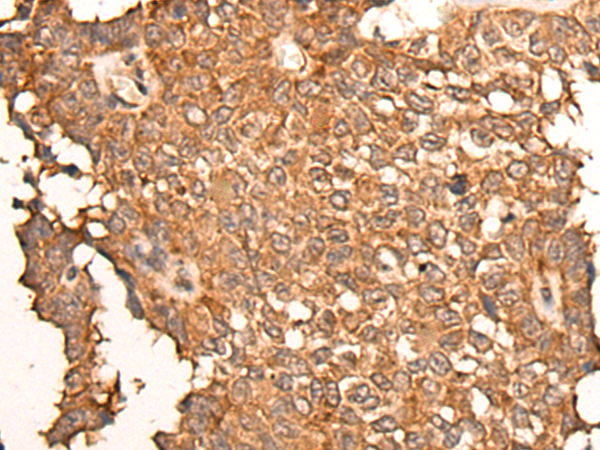

IHC positive control:

Human liver cancer and human breast cancer